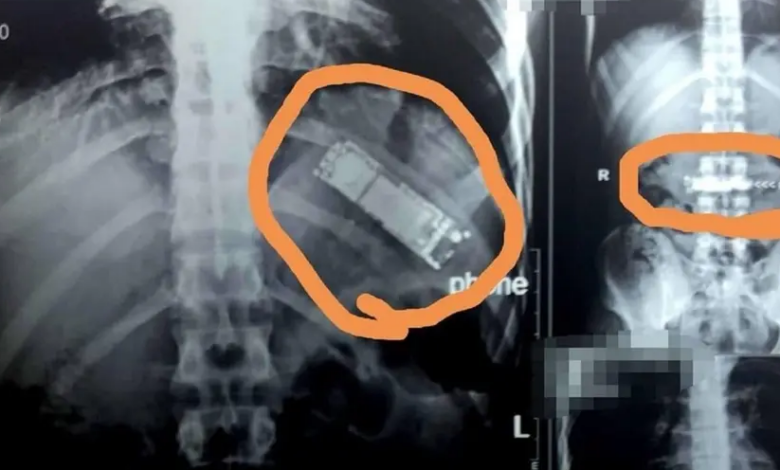

في حادثة غريبة، تمكن فريق طبي في مصر من استخراج هاتف محمول من معدة مواطن مصري كان قد ابتلعه منذ 7 أشهر.

ووصل المواطن حسن رشاد البالغ 28 عاماً إلى مستشفى بنها الجامعي، حيث كان يشكو من آلام بمعدته تعاوده من فترة لأخرى، وبفحصه وإجراء اللازم تبين وجود جسم غريب داخل بطنه.

كما أظهرت الفحوصات أن هذا الجسم الغريب هو هاتف جوال فيما قال المريض إنه ابتلعه خلال لحظة مزاح بينه وبين زملائه، لافتاً إلى أنه لم يبلغ أسرته بالواقعة ظناً منه أنه وبمجرد أن يقوم بالقيء في أي وقت سيتمكن من إخراج الهاتف من معدته.